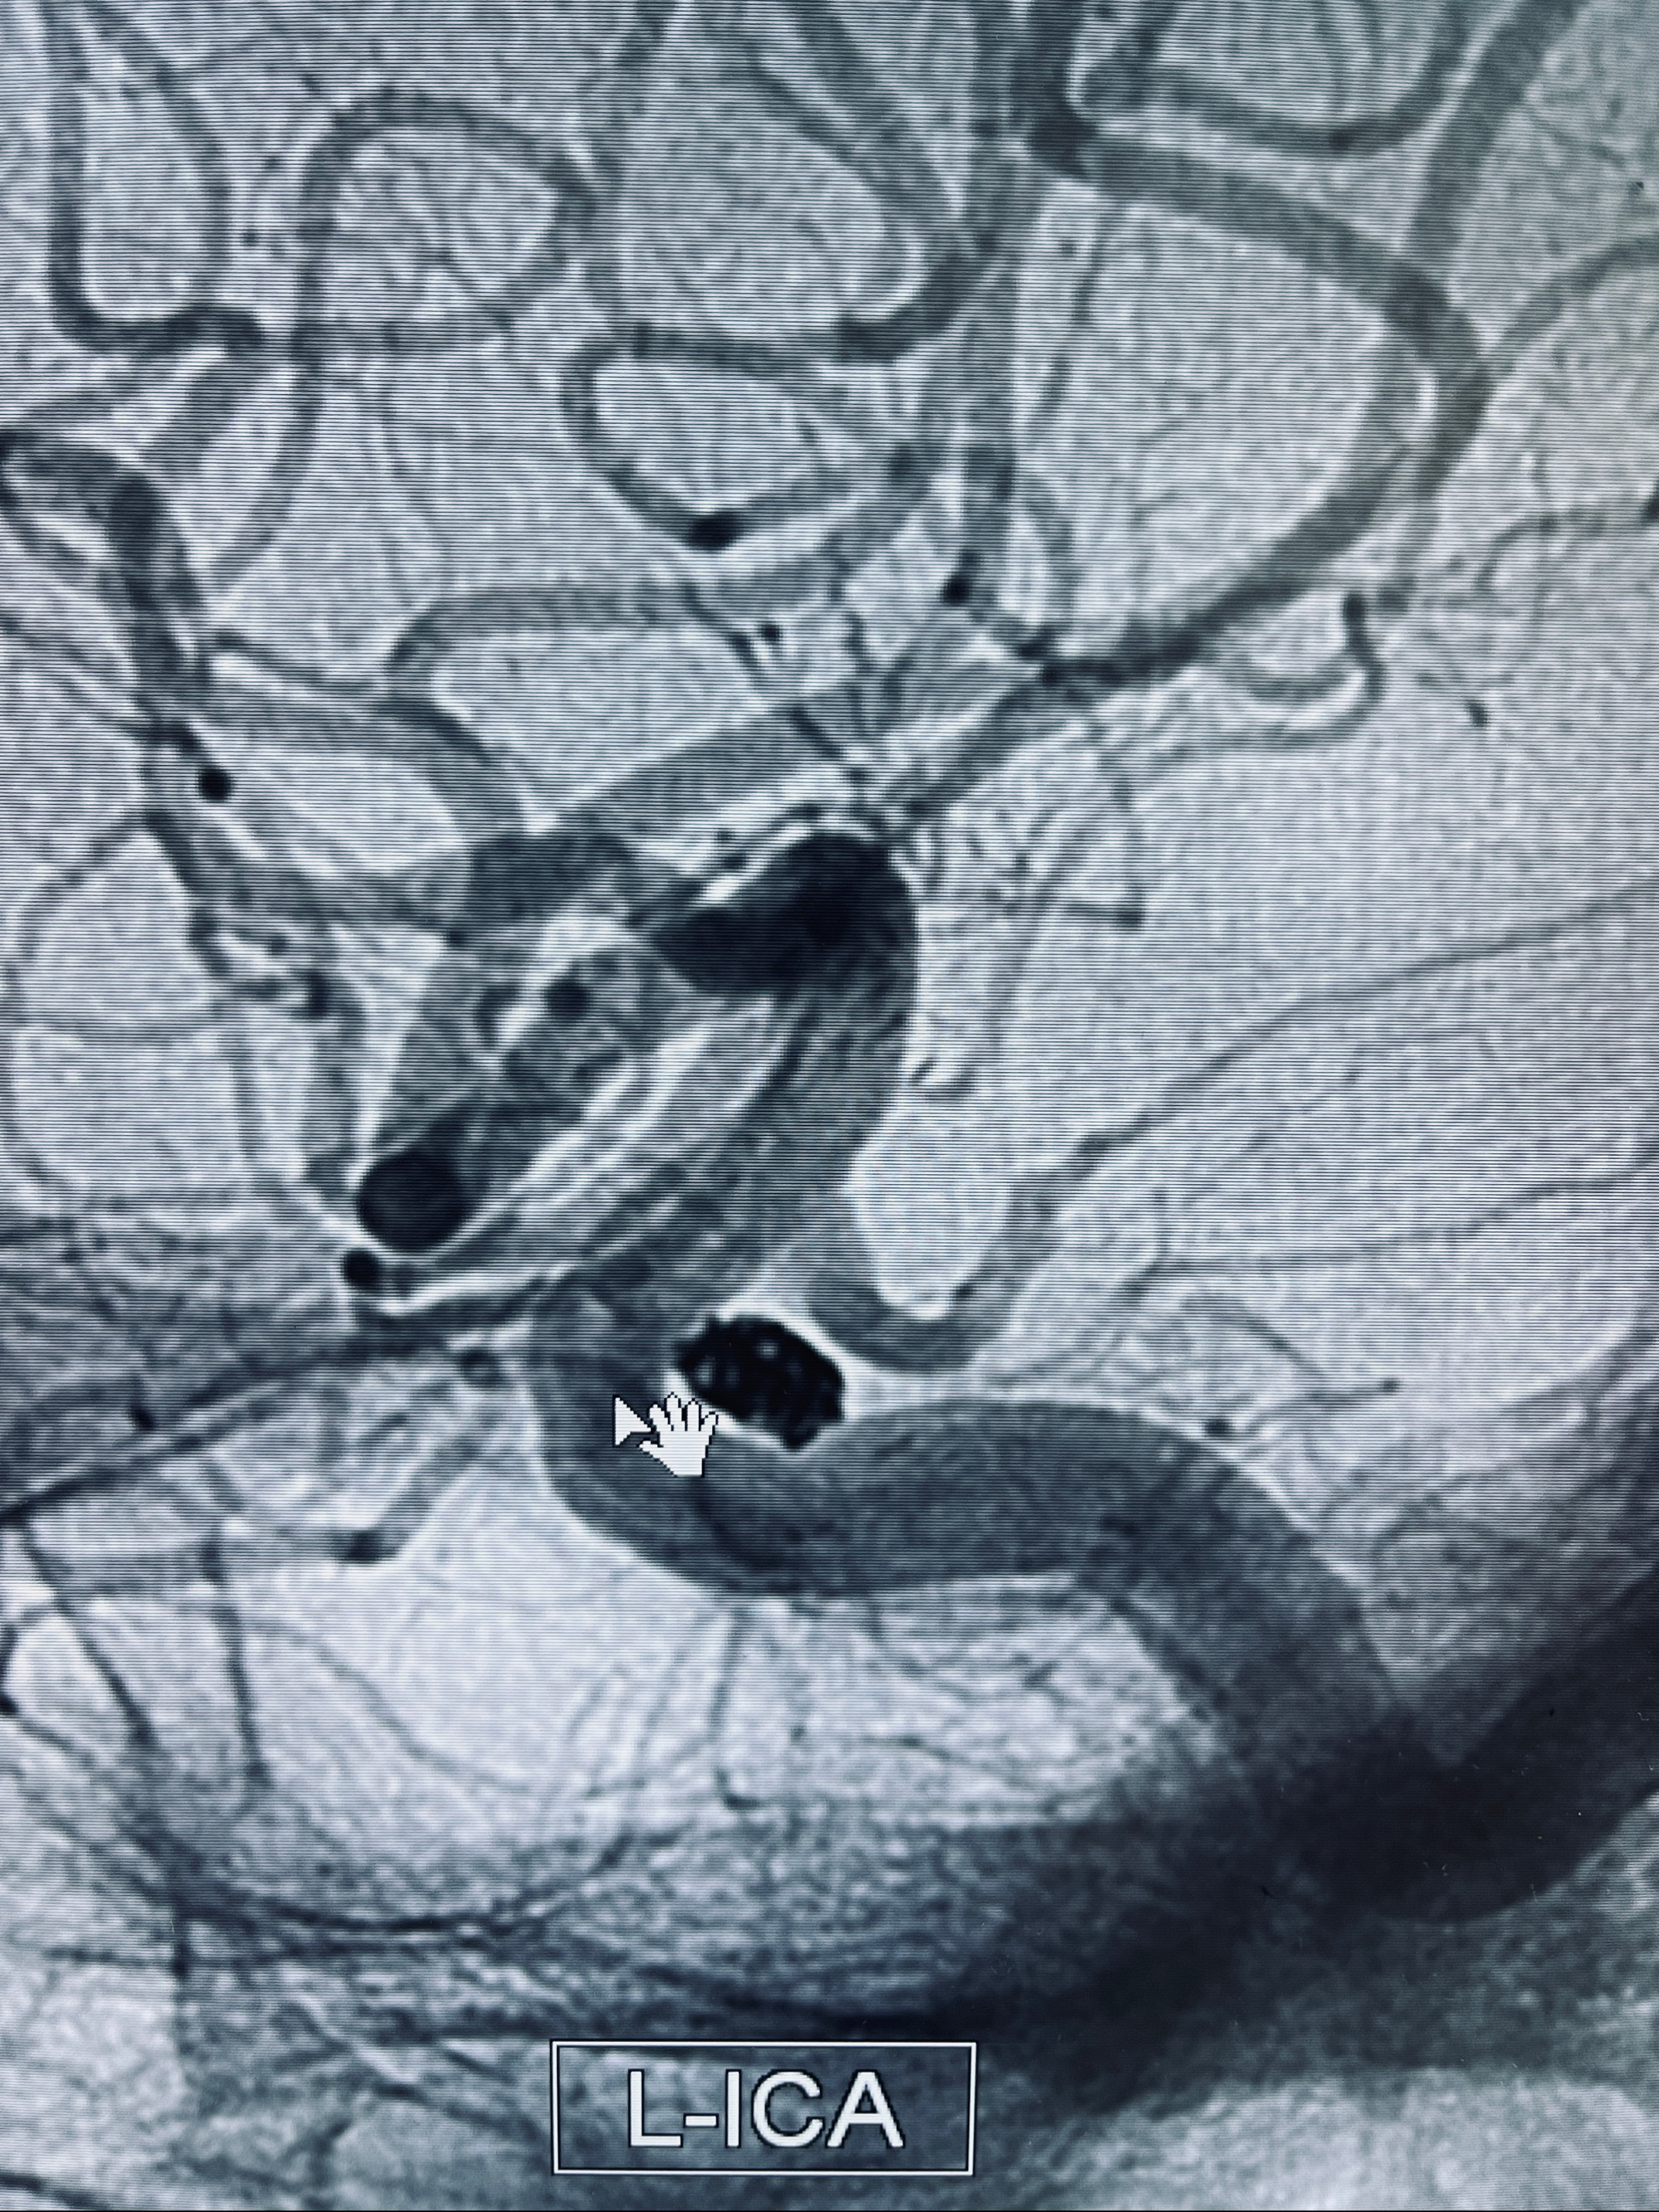

现病史:患者,女,因“左侧颈眼动脉瘤支架辅助栓塞术后1年余”入院。患者2021-5-24因“头晕”就诊于华山医院查头颅CTA、DSA诊断左侧颈眼动脉瘤,随后在全麻下行“左侧颈眼动脉瘤支架辅助栓塞术”,术顺,术后恢复可,予以阿司匹林、氯吡格雷抗血小板,阿托伐他汀钙片降脂稳定斑块。3月后华山医院复查脑血管造影动脉瘤未见明显复发或残留,停用降脂药物。目前患者无明显不适主诉,口服阿司匹林抗血小板治疗,为行脑血管造影收入我科。

1.左侧颈内动脉眼动脉段动脉瘤(支架辅助栓塞术后)

2022-09-29复查DSA

患者支架内血栓,给予阿司匹林+立普妥+依折麦布强化降脂干预